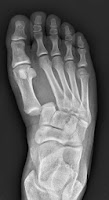

A Lisfranc injury, name after the French surgeon Jacques

Lisfranc de St. Martin is damage to the foot that causes metatarsals to be

dislocated from the tarsal bones. This usually involves the ligament that holds

the medial cuneiform to the second metatarsal base. These injuries can range

from a ligament rupture to multiple bone dislocations at the tarso-metatarsal

joints. The patient usually have an

injury of twisting or crushing of the foot such as motor vehicle accidents.

The patient from figure 1 had no

idea how he injured his foot but he has significant and multiple injuries.

The patient from figure 2

definitely knew he had an injury.

The patient in figure 3 knew he

had injured himself and sometimes injuries such as these are not recognized in

the emergency room.